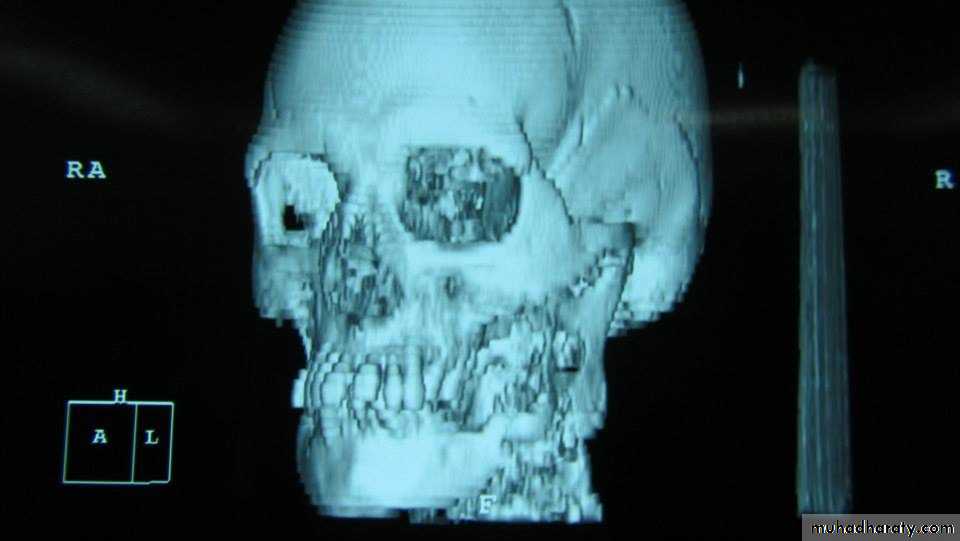

It is a tumor arising from embryonal cells of developing teeth. Although most forms of this tumor simulate other slow-growing benign tumors some can develop malignant tendencies.Patient may have few subjective symptoms during tumor growth. Enlargement of the tumor may expand the buccal, lingual or palatal bone plates. Tooth may be loosen and pressure symptoms may occur.

include extirpation, radical resection of the jaw. selective block excision and electro cauterization. Local excision of usually accessible tumor is indicated in the young.Provided, that they agree to regular follow - up and a radical resection when recurrence occurs. Recurrences are not unusual after curettage incomplete surgical treatment may stimulate tumor cell growth.

which is a benign slow growing tumor of bone that tends to have its greatest growth in the second decade of life. it is a diffuse poorly differentiated endosteal tumor. replacing the normal spongiosa with fibrous tissues. The enlargement neoplasm may displace teeth and expand cortical plates of the jaw bones.Fibro-osteoma tends to occur more frequently in women than in man and is seen more often in the maxilla than in the mandible. The active fibro-osteoma or ossifying fibroma frequently recurs when surgical excision dose not include . 10 to 12mm margin or when treatment has been instituted at an early age. radical treatment is less likely to lead to a later recurrence. These tumors do not respond favorably to radiation therapy.